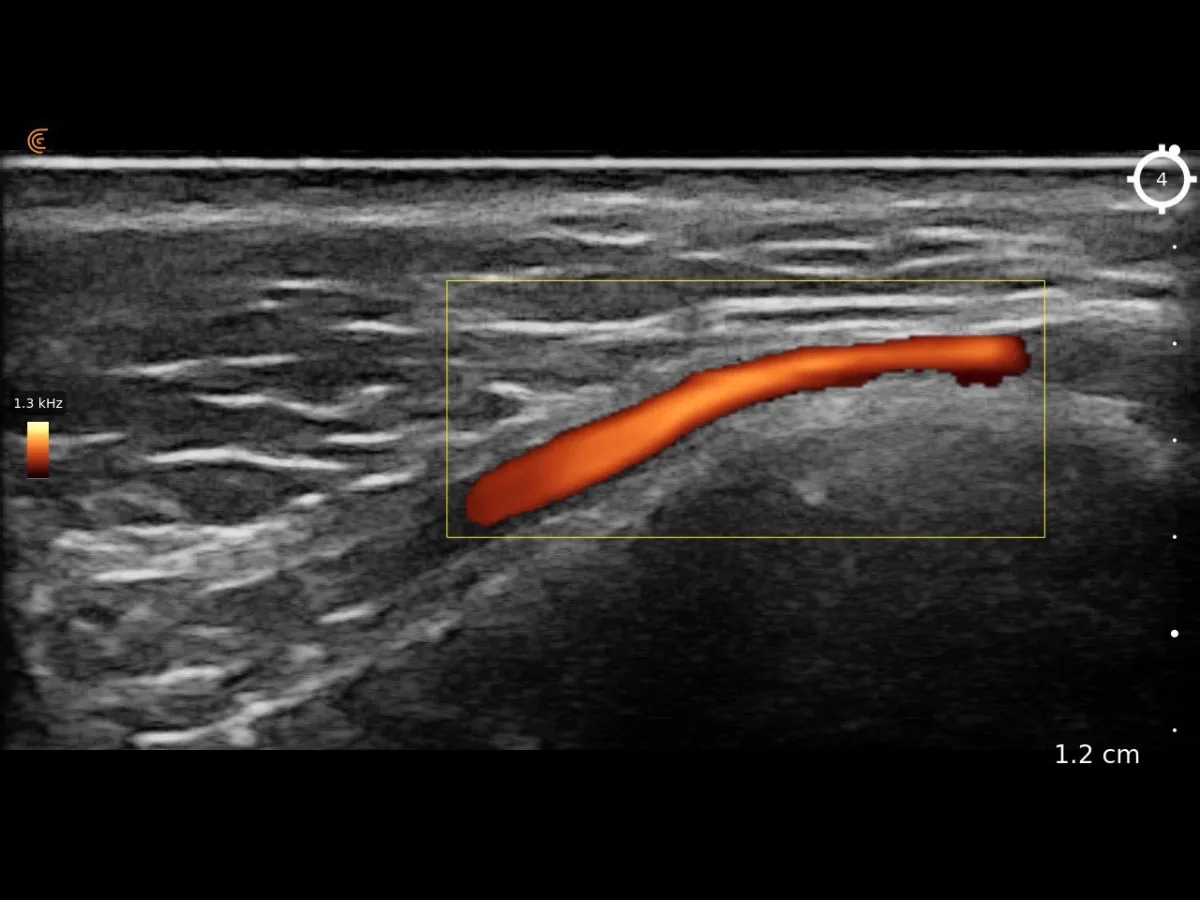

Doppler blood flow mapping

Detects vascular lesions and abnormal vessel patterns

Using Doppler imaging, Dr. Pang maps blood vessel involvement within lesions — essential for planning laser treatment or sclerotherapy with minimal risk.

Live Display & Doppler Imaging

Real-time tissue imaging and colour Doppler mode for blood flow mapping — every finding reviewed with you on screen, right then and there.